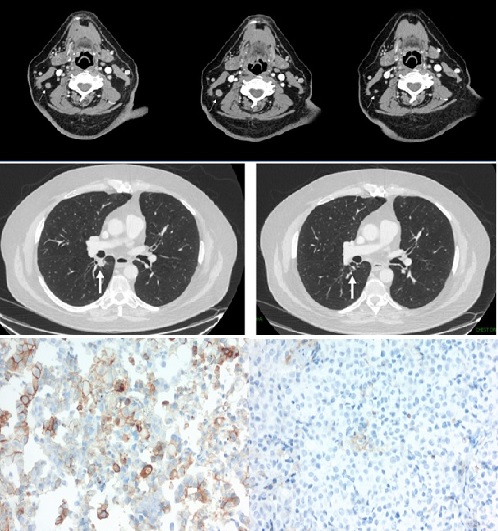

A Case Report of Acute Myeloid Leukemia in a Patient Treated with Pembrolizumab

Case Report

Clin Oncol Case Rep 2021, 4:1 (156)

Case Report

Clin Oncol Case Rep 2021, 4:1 (157)